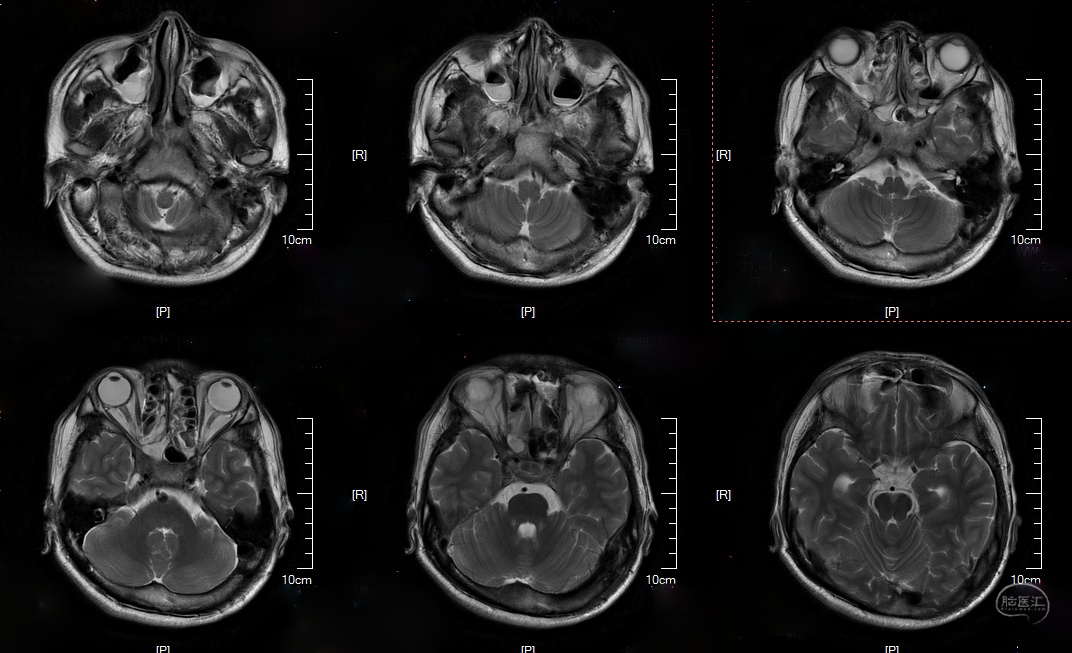

术前影像

头颅CT及MRI:

DWI:

T2:

T1:

T2 flair: